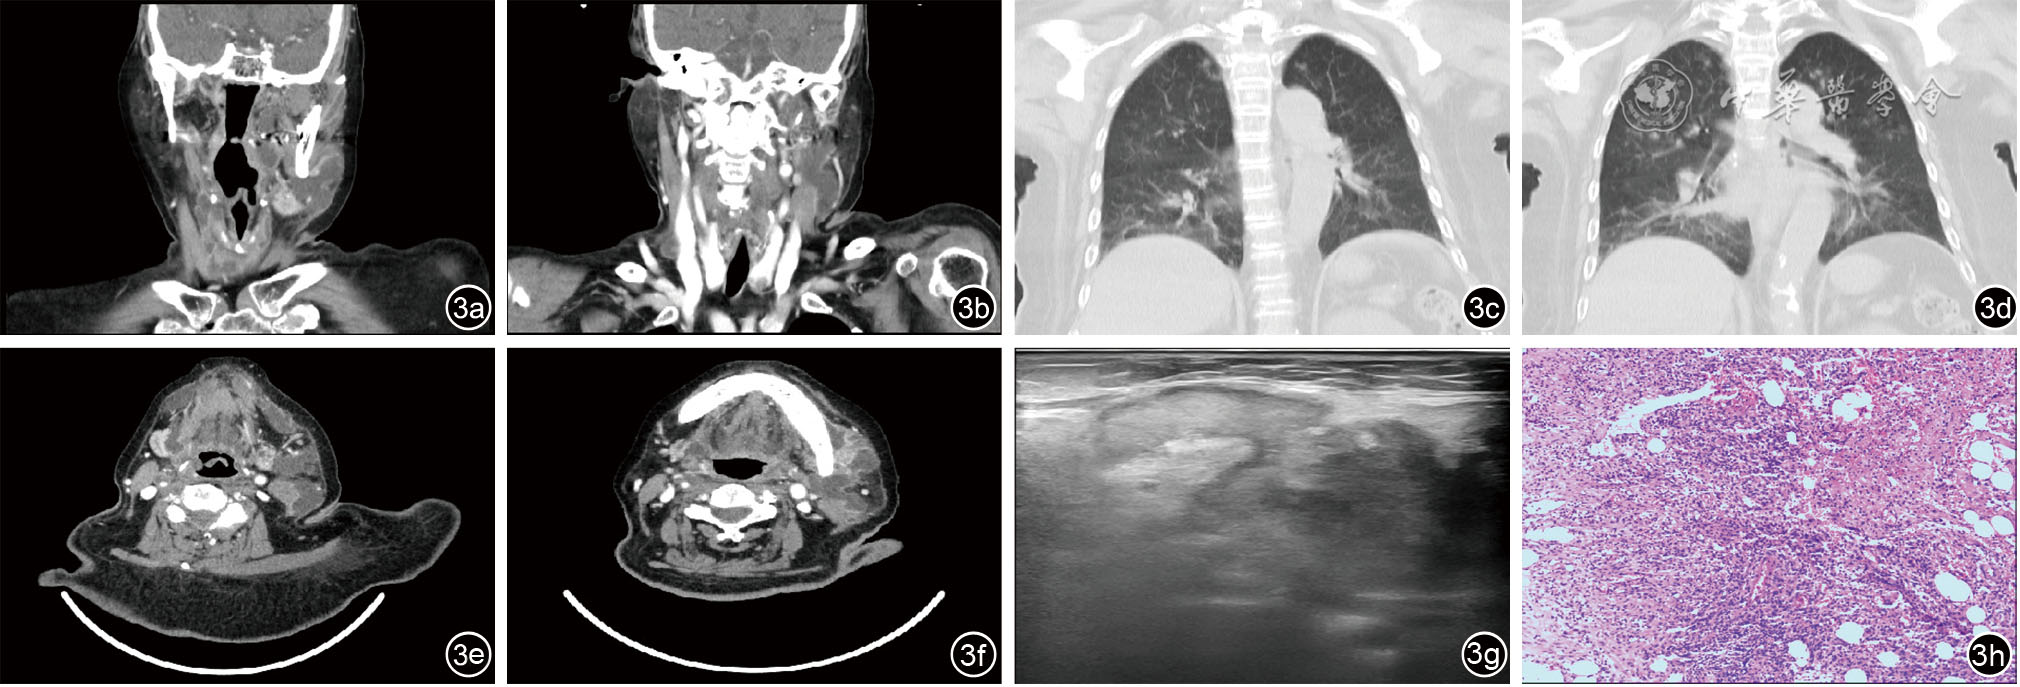

图3 病例三患者影像病理学资料。图3a~3b为颈深间隙感染患者术前颈部CT;图3c~3d为术前胸部CT;图3e~3f为术前颈部CT增强;图3g为术前颌下浅表肿物彩超;图3h为术后快速病理图像切片

3 女性 76 颈深部脓肿,扁桃体炎,咽溃疡,肺部感染,低白蛋白血症,高血压病3级(极高危),贫血,2型糖尿病性视网膜病变,完全性左束支传导阻滞,房性早搏,心功能不全,脑梗塞个人史,急性左心衰,呼吸衰竭 喉咽部前部皮下、咽旁间隙多发低密度灶

经颈咽旁间隙病损切除+双侧咽旁、颌下、颏下、气管旁间隙、甲状腺前脓肿切开排脓引流术 (颈深部)炎性肉芽组织。 未愈